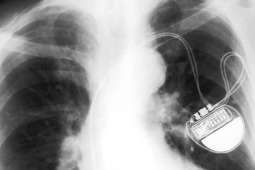

Lekarze ze Szpitala Klinicznego Przemienienia Pańskiego w Poznaniu wszczepili dwóm pacjentom kardiowertery-defibrylatory. Jak mówią przedstawiciele placówki, to najprawdopodobniej pierwsze użycie nowej wersji tych urządzeń w Polsce.

- Zabiegi wszczepienia urządzeń są wykonywane w Polsce od około 20 lat. Tym razem jednak wszczepiliśmy kardiowerter-defibrylator jednojamowy, który potrafi z dużą precyzją rozpoznać migotanie przedsionków. Do tej pory rozpoznanie tego rodzaju arytmii przy użyciu urządzeń wszczepialnych było zdecydowanie bardziej skomplikowane, wymagało urządzeń dwujamowych - powiedział dr hab. Przemysław Mitkowski z Kliniki Kardiologii Szpitala Klinicznego Przemienienia Pańskiego Uniwersytetu Medycznego w Poznaniu, o czym może przeczytać na portalu "Wyborcza.pl".

- To chorzy z niewydolnością serca i z wysokim ryzykiem wystąpienia zagrażających życiu komorowych zaburzeń rytmu. To jest wskazanie do wszczepienia tego urządzenia. Urządzenia wszczepialne są także najlepszym narzędziem do rozpoznawania migotania przedsionków, gdyż arytmia ta bardzo często ma charakter bezobjawowy - wyjaśnił Przemysław Mitkowski.

Wersja kardiowertera-defibrylatora, która została użyta w zabiegach została dopuszczona do użycia w Unii Europejskiej niespełna dwa tygodnie temu.